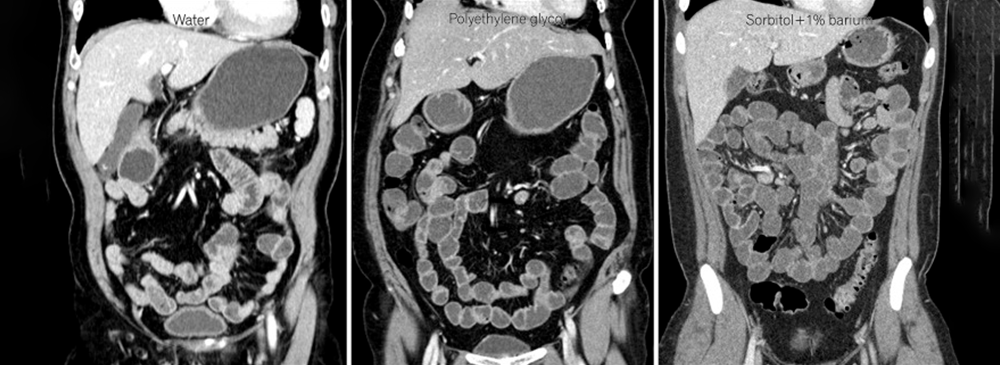

Unlike routine CT scans, CT Enterography focuses closely on the small intestine — a section of the digestive tract that is notoriously difficult to assess through standard imaging. By combining a powerful CT scanner with a special oral contrast solution, this test produces highly detailed images that reveal inflammation, bleeding, tumors, strictures, or other abnormalities that may be causing your symptoms.

CT Enterography is a diagnostic test that uses advanced CT technology and a special oral contrast solution to produce detailed images of the small intestine and surrounding abdominal structures. Unlike traditional CT scans, which provide a general view, CT Enterography is tailored to highlight the intestinal walls and blood vessels, giving doctors a much clearer picture.

The oral contrast works by filling and outlining the small bowel, which allows the scanner to capture high‑resolution cross‑sectional and 3D images. This makes it possible to detect even subtle changes such as early inflammation, hidden bleeding, strictures, or abnormal growths. In some cases, an intravenous (IV) contrast dye may also be used to provide additional details about the blood vessels and surrounding tissues.